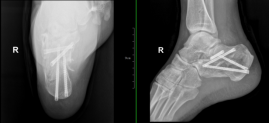

术前照片

术后照片